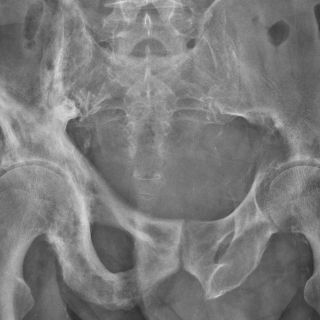

En México, cifras de la Asociación Mexicana de Metabolismo Óseo y Mineral (AMMOM) reportan que al menos 17 por ciento de las mujeres y alrededor de 9 por ciento de los hombres, de 50 años y más, sufren osteoporosis en la columna lumbar, mientras que en ese orden 16 y 6 por ciento la padecen en la cadera.